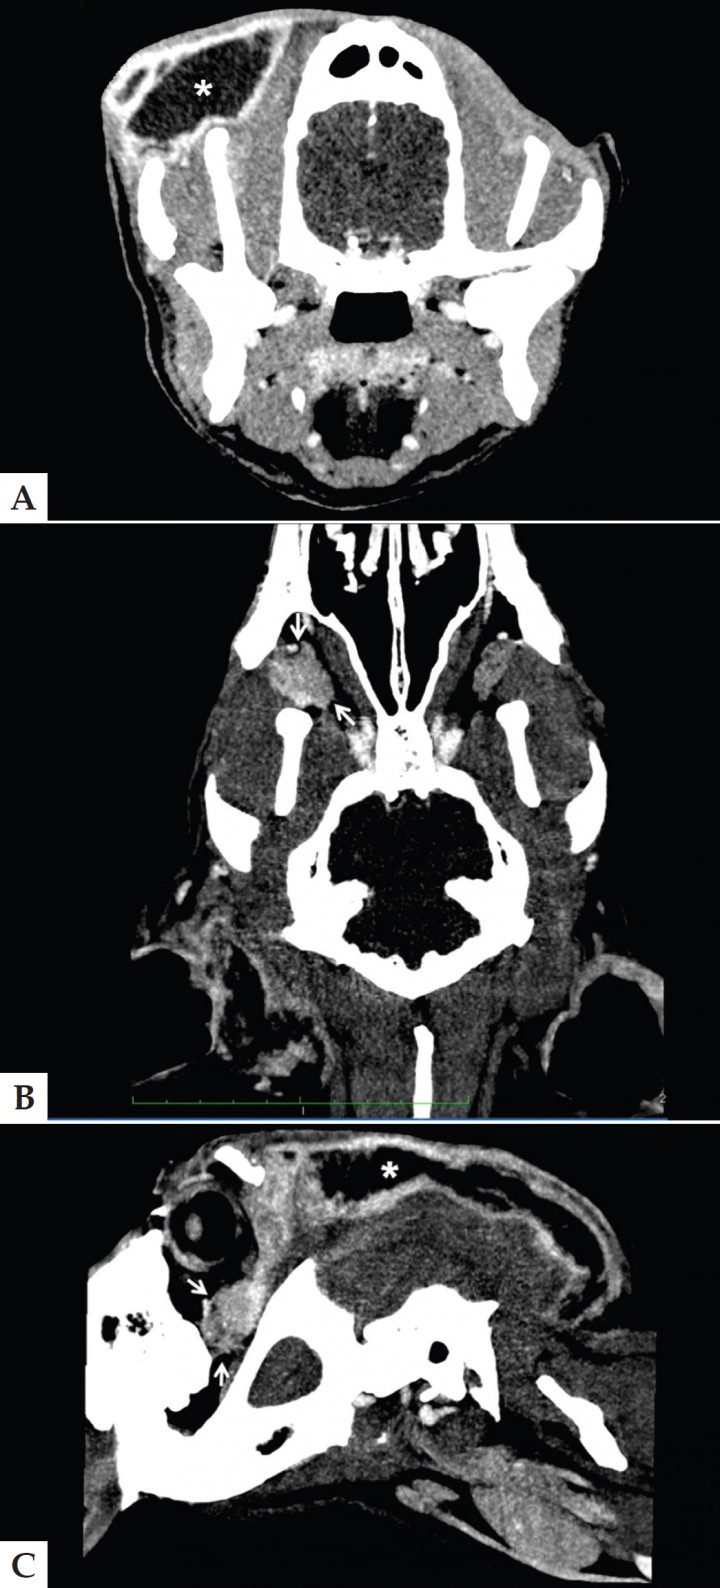

Para valorar la extensión y posible origen del absceso se realizó una TC bajo sedación profunda. En las imágenes post-contraste (contraste empleado: Iopramida, 2 ml/Kg/IV, Ultravist, 300 mg/ml, Bayer, España) se observó una masa quística con contenido líquido, localizada en tejido subcutáneo y comunicada en la porción rostral con la glándula cigomática derecha, extendiéndose caudalmente hasta la región occipital. La glándula cigomática aparecía hipodensa, aumentada de tamaño y con una captación de contraste moderada y heterogénea (Fig. 1). Estos hallazgos eran compatibles con la presencia de una sialoadenitis cigomática y un absceso retrobulbar asociado que se extendía por el espacio subcutáneo en la región frontotemporal derecha, pero en base a las características tomográficas no se podía descartar la presencia de una neoplasia glandular.

<p>Imagen de tomografía computarizada postcontraste el día de la visita (A. Axial; B. Dorsal; C. Parasagital) en la que se observa un aumento de tamaño de la glándula cigomática derecha (flecha) con captación de contraste marcada y heterogénea que se comunica con un acúmulo de material hipodenso subcutáneo bien encapsulado que se extiende desde la región frontal hasta la occipital (*). Ancho de ventana 142 UH. Centro de ventana 95 UH.</p>

Imagen de tomografía computarizada postcontraste el día de la visita (A. Axial; B. Dorsal; C. Parasagital) en la que se observa un aumento de tamaño de la glándula cigomática derecha (flecha) con captación de contraste marcada y heterogénea que se comunica con un acúmulo de material hipodenso subcutáneo bien encapsulado que se extiende desde la región frontal hasta la occipital (*). Ancho de ventana 142 UH. Centro de ventana 95 UH.